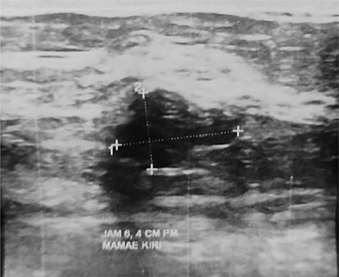

Post-Treatment UWBI

Post-operative findings on US are similar to mammogram and MRI, although the current recommendation of NCCN does not mention UWBI-based imaging as essential in this stage (Figure 4) (7). Seroma, hematoma, and lymphedema are commonly depicted as anechoic fluid collections. Solid to cystic nodules can be observed as well, and some of these may be resorbed completely as the healing process occur. The occurrence of lymphedema should raise an awareness for possible delayed breast cellulitis, as seen among patients who had surgery in upper lateral segment of the breast. Skin thickening findings are benign, and usually appear as bright echogenic lines with hypoechoic dermis (63, 67, 68). Fat necrosis appears as a solid hypoechoic mass mostly with posterior acoustic shadow since it is a complex of intra-cystic or solid masses. While cystic masses possess internal echogenic bands, which is highly influenced by the patients’ current position, solid masses have circumscribed or ill-defined margins due to alterations of breast parenchyma area (69).